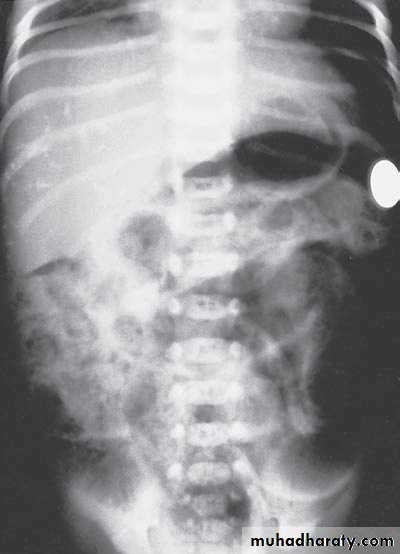

N.E.C

Hirschprungs disease